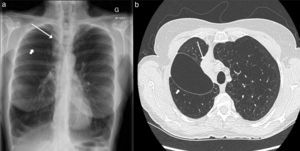

En los 3 meses siguientes, la paciente no mostró una mejoría clínica o funcional significativa. Los estudios de imagen mostraron la presencia de una cavidad aérea interlobular no resuelta y atelectasia persistente en el LSD (fig. 1). Se sospechó que esta voluminosa cavidad neutralizaba el efecto beneficioso de la reducción de volumen obtenida mediante la atelectasia del LSD, por lo que se decidió retirar las válvulas restantes. La válvula apical resultó inaccesible debido a la angulación del bronquio, pero la válvula posterior pudo extraerse con éxito.

La atelectasia del LSD y la cavidad aérea interlobular persistieron a pesar de la extracción de la segunda válvula. Ello motivó la colocación guiada por TC de un drenaje torácico en el interior de la cavidad aérea, que reveló una fuga de aire perpetua que explicaba el neumotórax prolongado (de más de 3 meses de evolución tras el procedimiento inicial). La paciente fue derivada a cirugía torácica para tratar de contener el neumotórax y lograr la reducción pulmonar. La atelectasia lobular de la paciente hizo que la elección de la intervención quirúrgica fuese una lobectomía superior derecha en lugar de una LVR clásica. Con esta intervención se logró el cese de la fuga de aire, lo que permitió retirar el drenaje torácico 3 días más tarde. En las visitas de seguimiento efectuadas en los meses siguientes a la LVR quirúrgica no se observó mejoría clínica o funcional significativa, y la paciente fue derivada para la evaluar la posibilidad de efectuar un trasplante pulmonar.